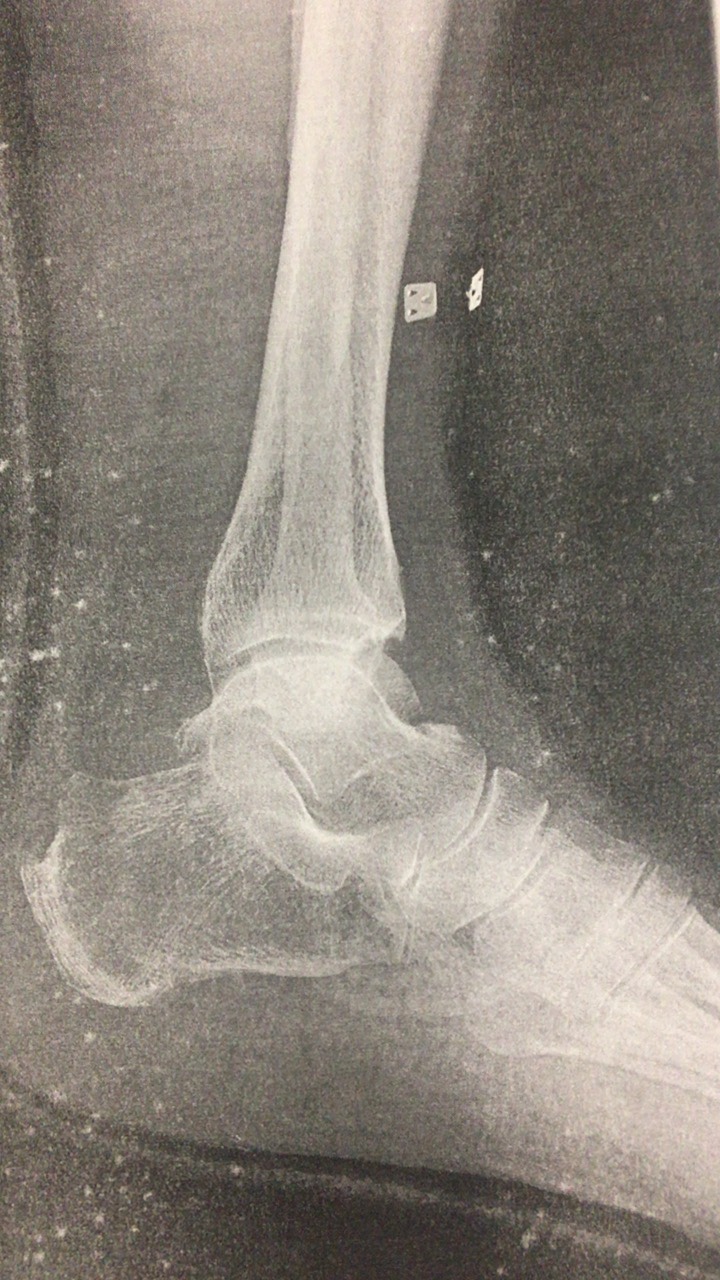

踵の痛み 成長期のシーバー病と大人の有痛性踵骨棘の共通点